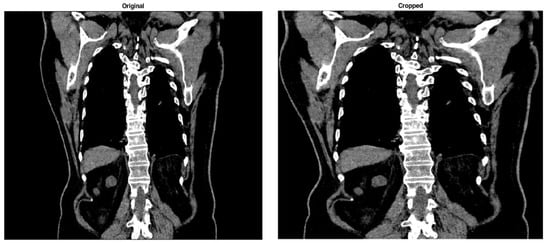

3.1. Image Black Border Removal